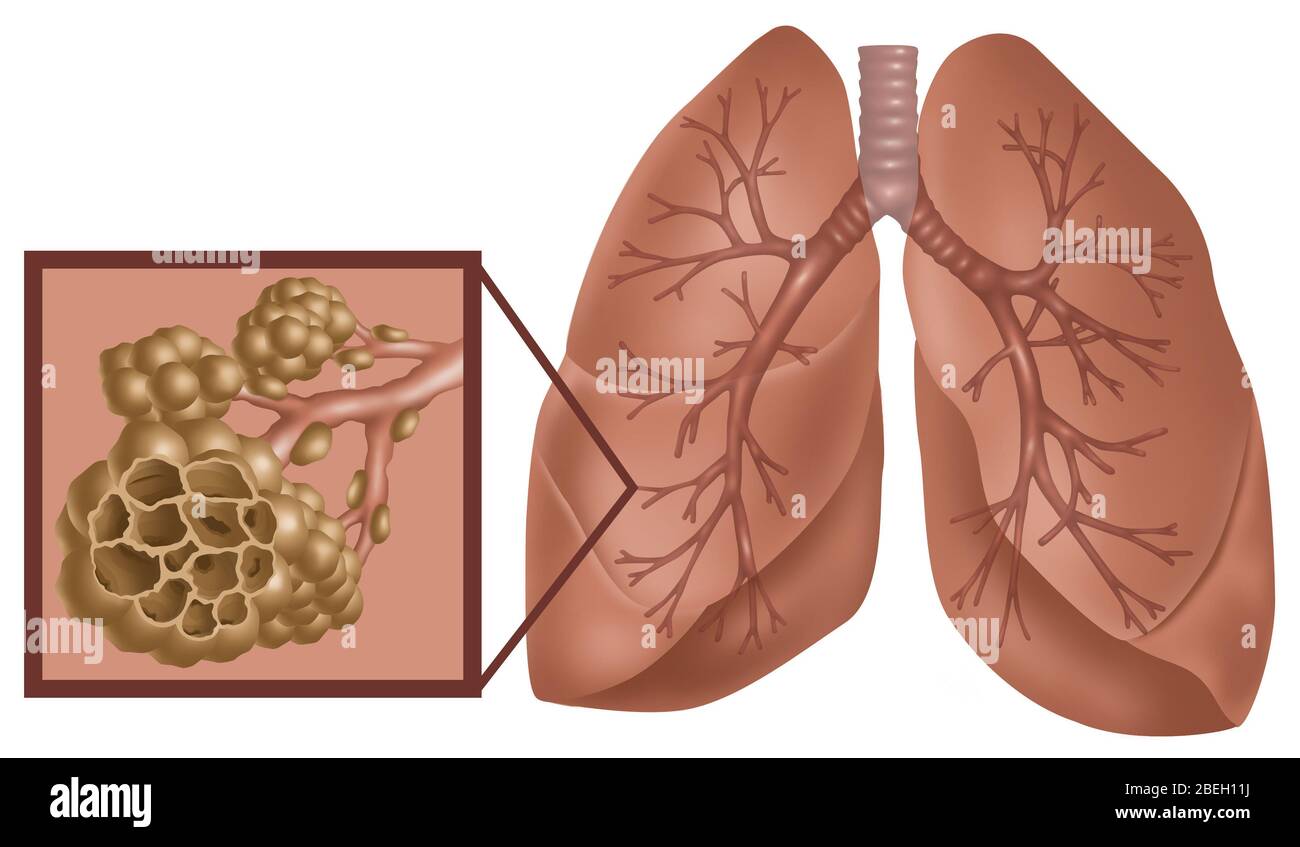

alveoli lung lungs gas exchange pulmonary anatomy alveolus membrane blood structure respiratory function microscopic supply infection disease

Lung anatomy & function. Alveoli bronchioles anatomy edu adapted. Organs and structures of the respiratory system